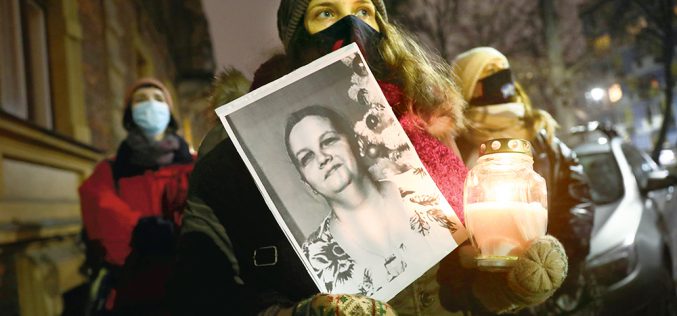

Prawo znowu zabija kobiety

Agnieszka trafiła do szpitala w pierwszym trymestrze ciąży bliźniaczej. Lekarze zwlekali z usunięciem obumarłych płodów